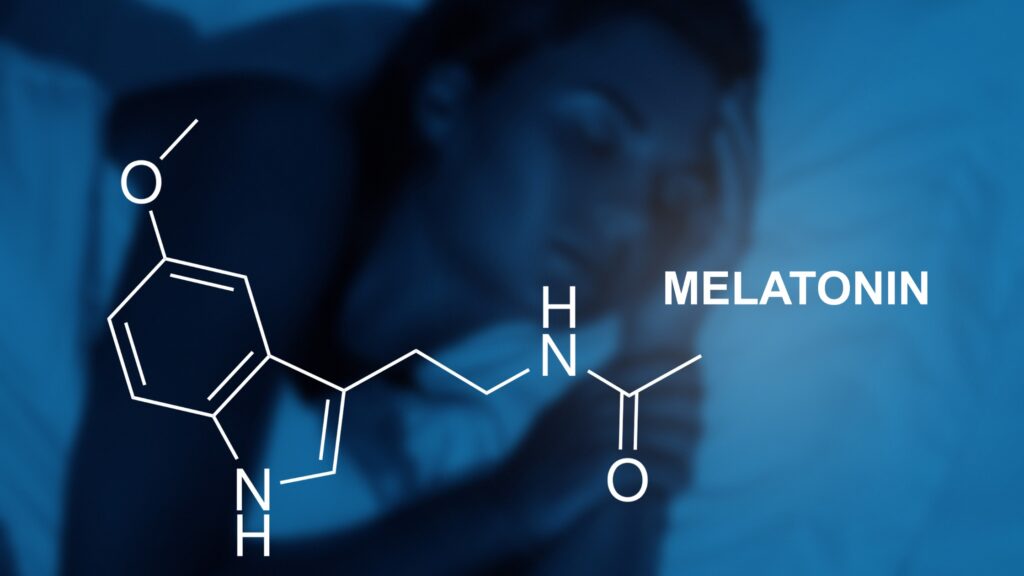

The Truth About Melatonin And Babies

We have all heard the stereotypes and the jokes about babies not sleeping very well for their first few months and how that basically means that the parents don’t sleep for that time period as well. Have you ever stopped to ask yourself why babies don’t sleep for long periods of time after they are … Read more

Supplements To Aid In Sleeping For Children

In today’s world of modern medicine, it’s so easy to try to solve just about every problem with a pill, but does that work for children? If your child is having trouble sleeping, especially if they are a young baby or toddler, then there may not be very many options for you to try in … Read more